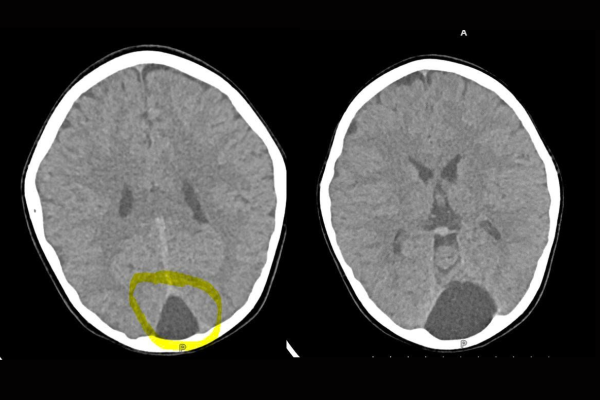

Trẻ 66 tháng tuổi đau nửa đầu đột ngột, nôn ói – Phát hiện nang màng nhện hố sọ sau qua chụp CT sọ não